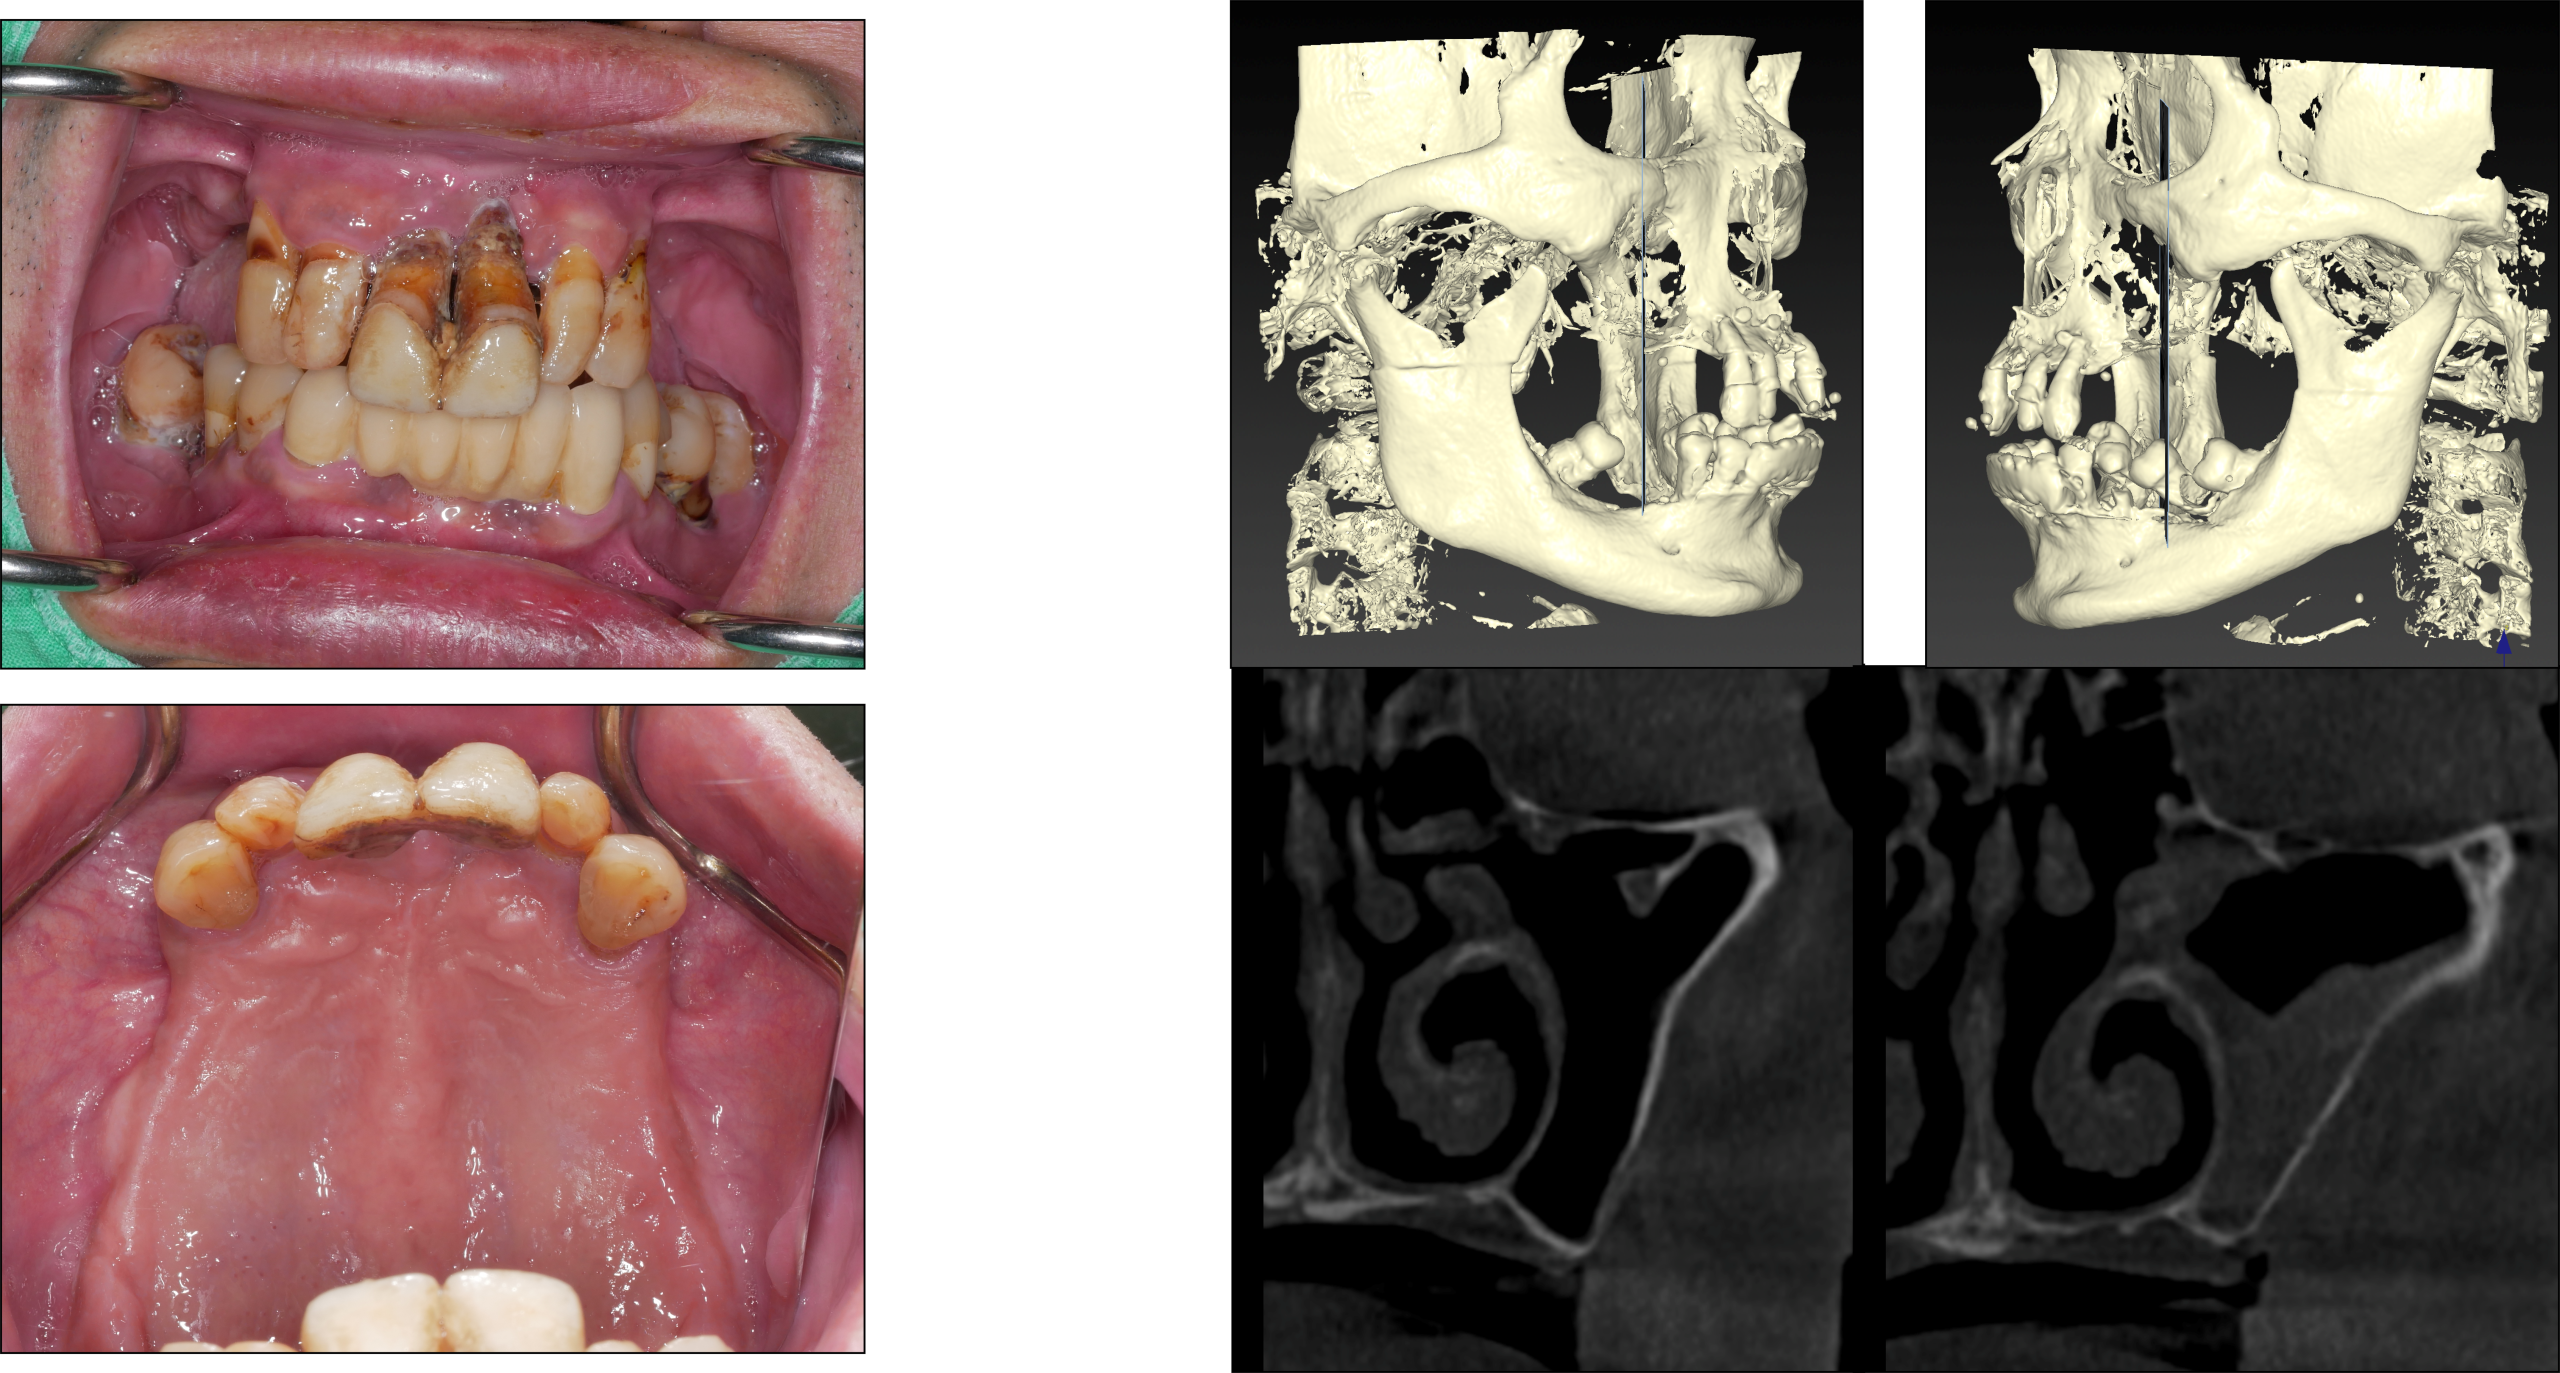

▍患者狀況說明

62歲男性,就診時,左側慢性鼻竇炎,曾接受過FESS手術處理,沒有慢性疾病,抽菸已戒除。

患者主訴:牙齒鬆動,後牙區缺失。

處理過程:口腔衛生不佳,上顎骨後牙區鼻竇底Crestal bone很薄,前牙區basal bone也很窄。因此採用staged zygoma implants 治療方式。

▍手術前 特殊案例思考

Poor oral hygiene and very thin residual crestal bone height